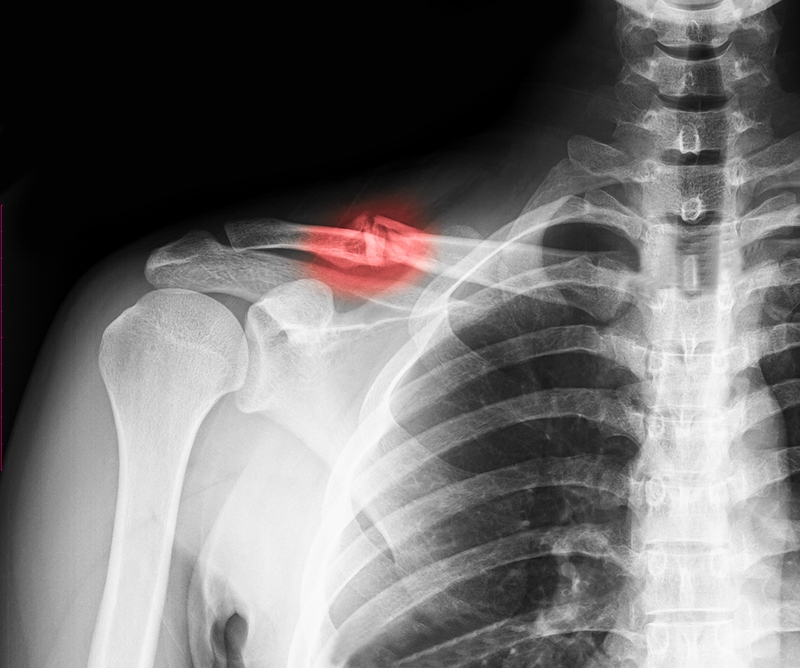

Sơ cứu gãy xương đòn như thế nào là đúng 1 Ảnh chụp X-quang của người bị gãy xương đòn

Khi bị gãy xương đòn, bệnh nhân có biểu hiện sưng, bầm ở vị trí gãy. Khi sờ hoặc ấn nhẹ vào vị trí này, nạn nhân có cảm giác đau nhói, có thể cảm thấy đầu xương gãy gồ lên ở dưới da và nghe thấy tiếng lạo xạo. Lúc này, nạn nhân rất khó để nâng cánh tay lên, chức năng vận động của vai cũng bị giảm hoặc mất hoàn toàn. Khi quan sát, có thể thấy vùng xương quai xanh bị biến dạng, lệch trục so với bên lành.

Trong trường hợp bệnh nhân bị gãy xương đòn hở, ổ gãy thông với bên ngoài qua vết thương trên da. Do đó, người sơ cứu có thể dễ dàng nhận định được tình trạng gãy xương của nạn nhân. Tuy nhiên, gãy xương hở là trường hợp nguy hiểm hơn rất nhiều so với gãy xương kín, cần cẩn thận đưa ra những phương án sơ cứu phù hợp để đảm bảo an toàn cho nạn nhân.